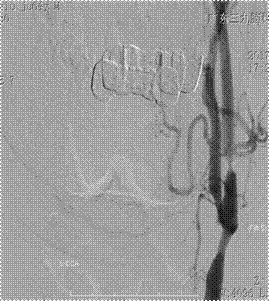

颅脑MRI提示:双侧基底节、放射冠区多发腔隙性脑梗死(如图一);颈部血管彩超提示:双侧颈动脉重度狭窄。3D-ASL提示:右侧额叶局部灌注减低,感兴趣区CBF测值为(28.39±12.97)mL/100g/min,低于对侧镜像感兴趣区测值(57.15±13.80)mL/100g/min(如图二)。DSA示:1、双侧颈内动脉起始部重度狭窄,狭窄程度均约90%,右侧狭窄长度约8mm(如图三);2、左侧颈总动脉末端中度狭窄,狭窄程度约50%,狭窄长度约1.0cm(如图四)。

图四